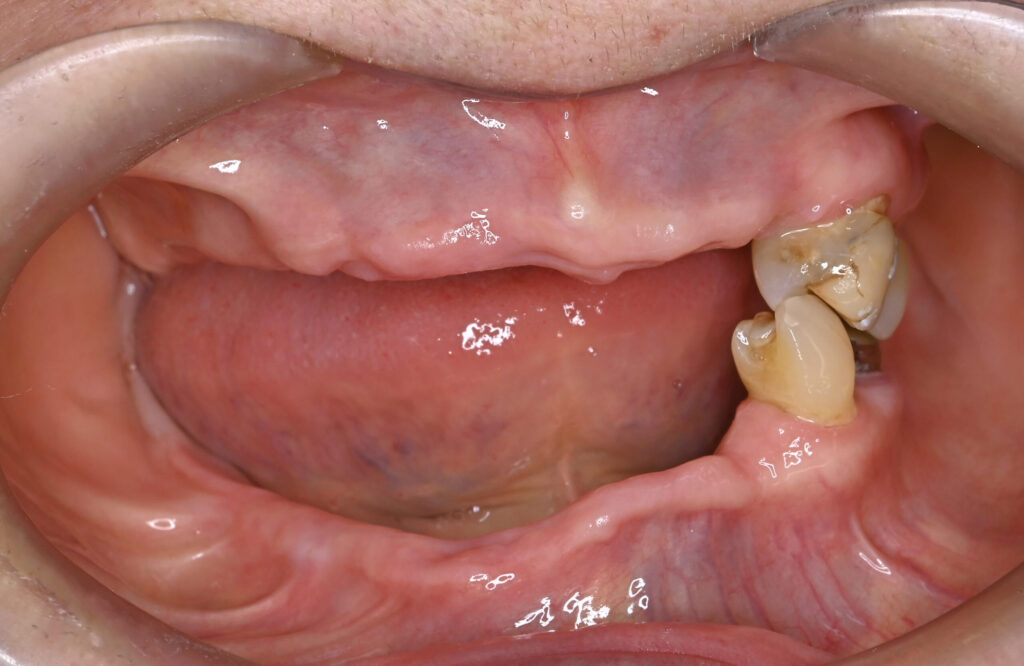

Before

After

治療期間・回数

約6ヶ月・約6回

費用

23,100,000円

治療のリスク

外科手術が必要になるため、患者様に体力的な負担がかかる。